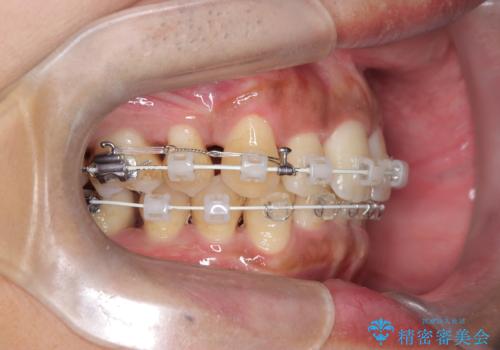

- 前歯のデコボコ(叢生)と、上下の歯の重なりが深い「ディープバイト(過蓋咬合)」を主訴にご来院されました。精密検査の結果、歯が並ぶスペースが不足しているため、上顎左右の小臼歯を抜歯することでスペースを確保し、全体の咬み合わせを改善する治療計画を立案しました。これにより、見た目の改善だけでなく、過度な咬み合わせによって生じる歯や顎への負担も軽減することを目指します。

今回の矯正治療では、まず歯が並ぶスペースを確保するため、上顎の小臼歯を抜歯しました。抜歯によってできたスペースを利用して前歯を奥へ移動させ、デコボコを解消。同時に、奥歯の咬み合わせを調整することで、深すぎた咬み合わせであるディープバイトも改善しました。治療の結果、長年気にされていた前歯のデコボコが解消され、理想的な歯並びに。さらに、正しい咬み合わせを獲得したことで、機能的にも安定した美しい口元になりました。